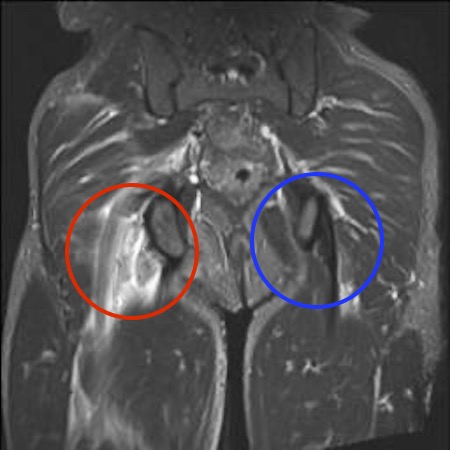

MRI

Complete / retracted tears

Proximal hamstring tear on right (red circle), normal insertion on tuberosity on left (blue circle)